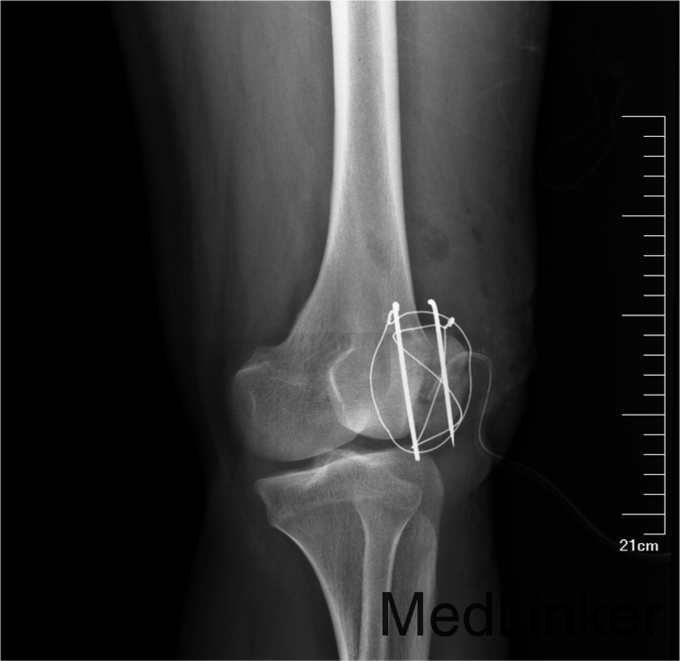

患者自述于2014年4月24日11点左右自马车坠落,摔伤致左膝关节疼痛、流血、活动受限,患者于当地医院行左膝X线检查,提示:左髌骨骨折,包扎,为进一步处理。患者现无意识障碍,无视物不清,无头晕、头痛,无恶心、呕吐,无胸闷及呼吸困难,无腹胀、腹痛。现平素饮食睡眠良好,二便如常。发病近期体重无明显下降。

左膝见一长约10cm的开放口,压痛(+)。未触及骨擦感及异常活动,未闻及骨擦音,患肢无明显 麻木,左下肢血运良好,余肢体查体未见明显异常。

患者入院后急诊行左髌骨清创缝合术,左髌骨骨折切开复位张力带内固定术。术后局部换药无红肿渗出,冷敷,甘露醇消肿,患肢抬高。患者术后14无不良主诉给予拆线。